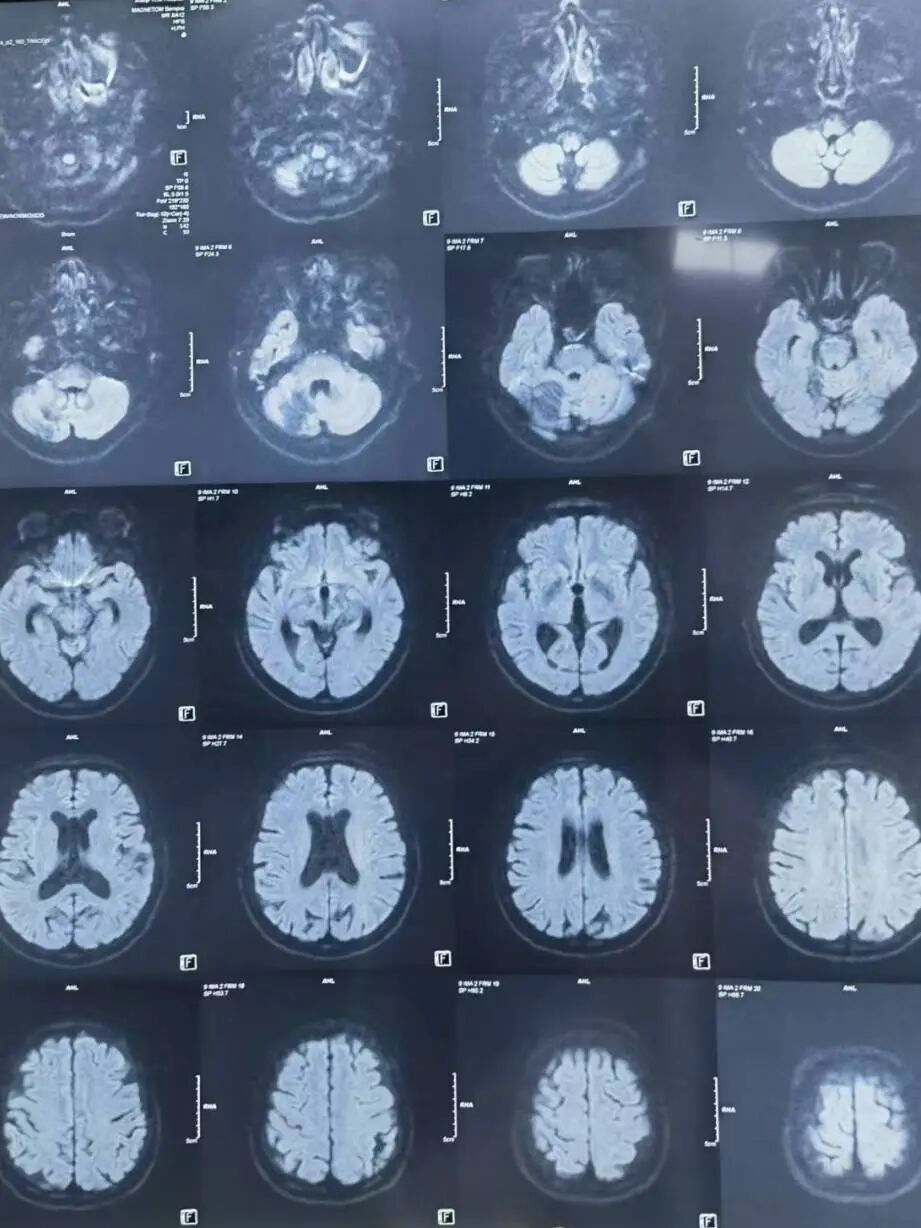

辅助检查:颅脑MR(当地医院):左侧小脑半球、双侧侧脑室旁、基底节区及双侧额叶皮层下多发腔隙性脑梗死;右侧小脑半球软化灶血管造影(当地医院)。颅脑MRA(当地医院):左侧颈内动脉后交通段局部膨大,可疑动脉瘤。 脑血管造影(当地医院) :左侧后交通动脉瘤。

颅脑MR (当地医院) :左侧小脑半球、双侧侧脑室旁、基底节区及双侧额叶皮层下多发腔隙性脑梗死;右侧小脑半球软化灶。